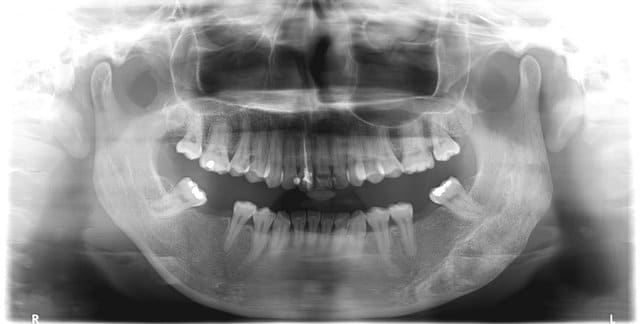

- Surplomb très important, recouvrement important. Egression du bloc incisivo-canin maxillaire.

- Faible calage postérieur (absence de 36-37 et de 46-47).

- Mésio-version de 38/48.

- Protrusion mandibulaire (cf position des condyles sur la panoramique, cf position/axe du cou dans la photo de profil) probablement une compensation posturale pour tenter de diminuer l'espace inter-labial.

- Endoalvéolies des secteurs latéraux et postérieurs mandibulaires et maxillaires.

- Décalage du milieu inter-incisif maxillaire vers la droite (léger) et mandibulaire vers la gauche (plus important). Cependant, sur la radiographie panoramique où nous retrouvons la même décalage, le condyle gauche est pourtant plus en avant que le condyle droit.

- Présence de plaque et gingivite autour de 15, 16, 17 et 25, 26, 27 (cf forme de la gencive sur les moulages).

- Très probablement interférences en propulsion sur 38/48.

- Inversé d'articulé sur 35.

- Il y a des traces rigolotes sur l'os mandibulaire gauche. C'est louche.

- Gros composites sur la 11 dévitalisée.

- Le plan d'occlusion semble plus bas à droite qu'à gauche.

- Syndrôme de long face (palais étroit, profond, cernes sous les yeux, visage allongé).

- Léger encombrement dans le secteur antéro-maxillaire.

> - Protrusion mandibulaire (cf position des condyles sur la panoramique,

La panoramique n'est pas fiable pour interpreter la position des condyle

> - Il y a des traces rigolotes sur l'os mandibulaire gauche. C'est louche.

+10

En effet c'est la raison pour laquelle la séance prise de documentation a tourner court. Quand la pano est revenu nous somme aller directement consulter de département de chirurgie. Toute considération esthétique devenant subitement très très secondaire.

Résultat des courses ce n'est pas cancereux, par contre la lésion peut évoluer en taille si c'est la cas et qu'elle atteint les dents elle les déplacera. La lésion semble stable mais nous avons un recul de seulement six mois. Une limitation est quand cas de chirurgie orthognatique si le trait de fracture passe sur cette lésion il y a une chance pour que l'os ne se consolide pas. Par contre ils peuvent meuler l'os sur l'extérieur sans risque pour réduire la taille de la lésion.